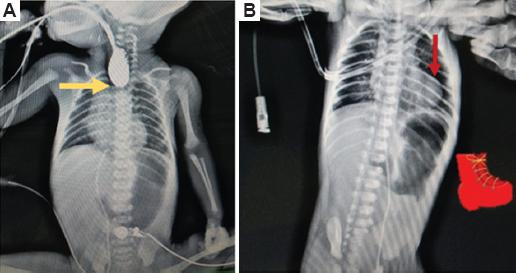

Al realizar un esofagograma baritado por la sospecha de atresia esofágica se observa el fondo de saco ciego a nivel de T2 (Fig. 4), siendo probable una atresia tipo III, la cual se confirma durante la cirugía.

Figura 4 A: esofagograma baritado que muestra un fondo de saco a nivel de la vértebra T2 (flecha). B: radiografía toracoabdominal con imagen característica de «zapato sueco» (flecha).

Por las características radiológicas del corazón, compatibles con la imagen en forma de «zapato sueco

» (Fig. 4), el soplo auscultado y la tonalidad de la piel, se solicita valoración por el servicio de cardiología pediátrica, que realiza un ecocardiograma y confirma una tetralogía de Fallot con las siguientes características: